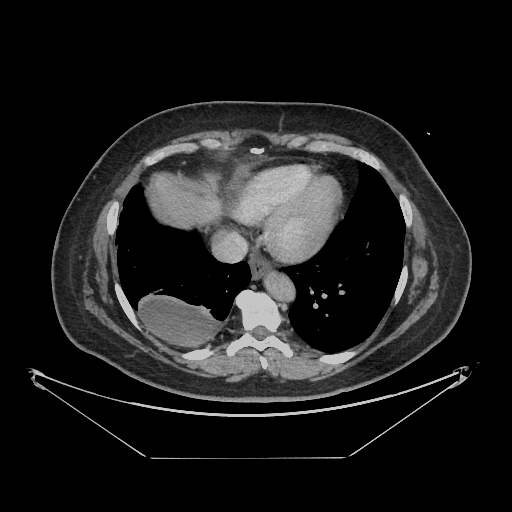

Generated VENOUS CT scan (A→B translation)

No window - Raw intensity values

Lung window (WL -600, WW 1500 β†’ Low βˆ’1350, High +150)

Mediastinum window (WL 40, WW 400 β†’ Low βˆ’160, High +240)